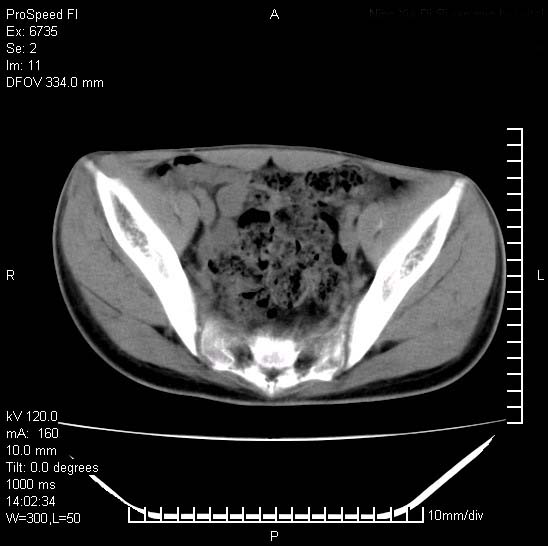

患者自诉胯部疼痛两年余,在当地服用中药,半月前至本院考虑骶髂关节结核,给予抗痨治疗。现发展至右下肢疼痛明显,活动受限,以膝关节处明显,拍膝关节平片无明显异常。

两侧骶骼关节改变,考虑强直性脊炎

左侧骶髂关节面限局性骨破坏,边缘硬化关节腔见钙化物;不出外tb

右侧骶髂关节也有类似改变,只是较左侧轻,首先考虑强直性脊柱炎,不除外结核,建议作hla-b27检查。

典型强脊炎改变,髋关节亦有累及

符合强直性脊柱炎表现。